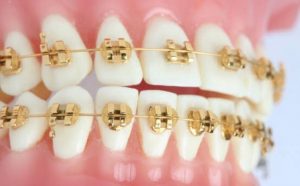

Tratamientos Ortodoncia Blanqueamiento dental Zoom Contacto 72 2795 9597 Marcar Ahora Envia whatsapp Visita nuestro facebook